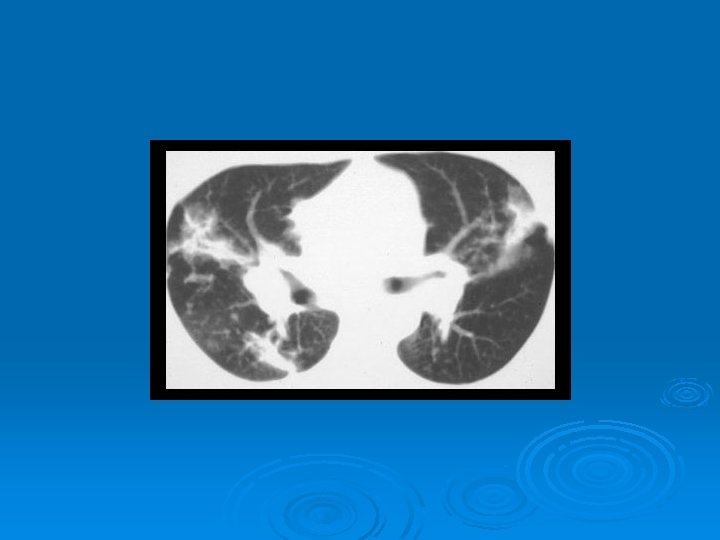

DEĞİŞİK RADYOLOJİK GÖRÜNÜMLER RETİKÜLONODÜLER PATERN

ASİNER PATERN

PNÖMONİK GÖRÜNÜM

ALVEOLER SARKOİDOZ

KAVİTER SARKOİDOZ

HRCT Ø Akciğer grafisine göre daha duyarlı Ø Paratrakeal, pretrakeal, paraaortik ve subkarinal adenopatilerde tespit edilebilir